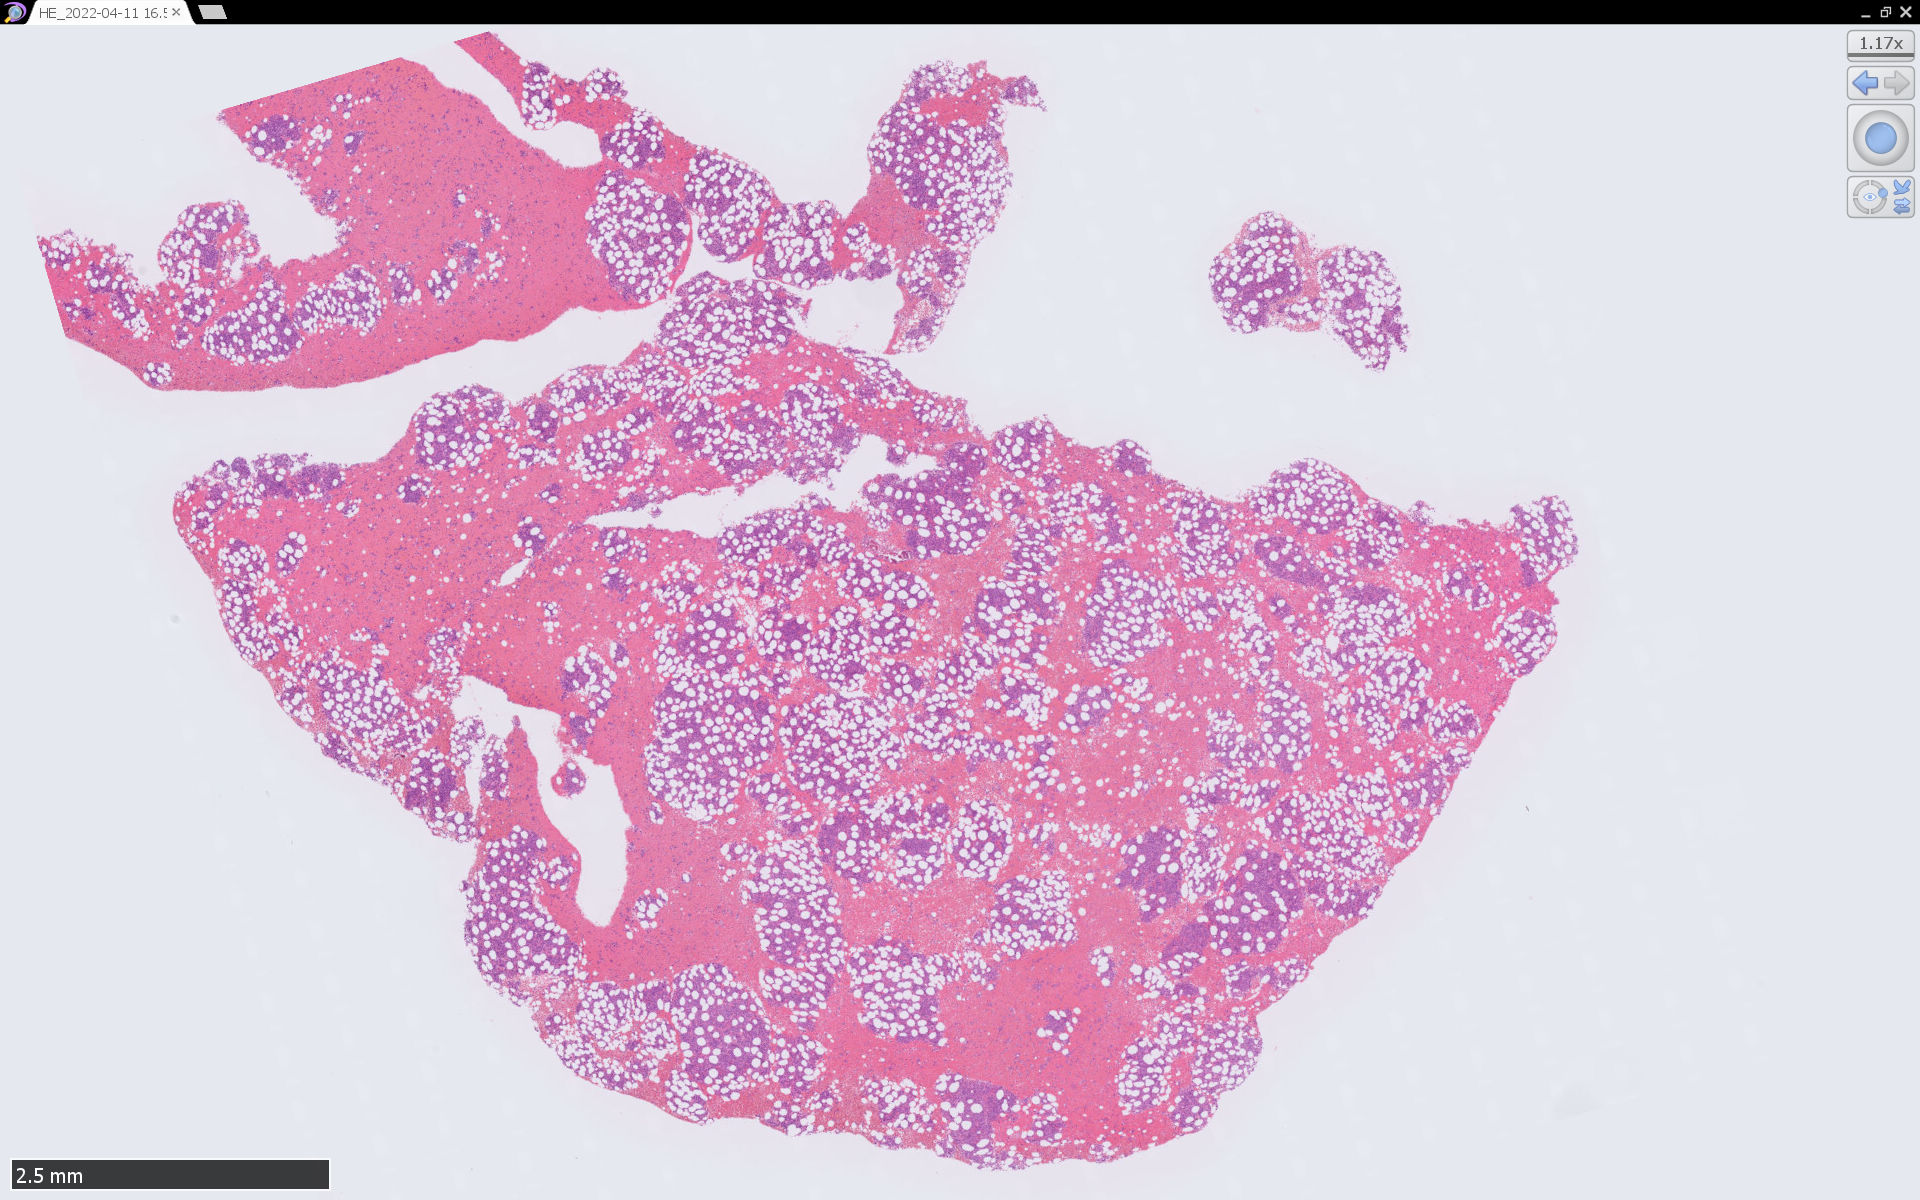

骨髄病理所見

組織, 細胞病理

皮膚病変

腫瘍細胞は真皮を主座として, 皮下脂肪織まで, びまん性かつ単調monotonousに増殖することが多く, 表皮向性はみられない.

腫瘍は形態の異なる2種類の細胞の均一単調な増殖からなる.*4

1. classical BPCDN

腫瘍細胞核は中等大, 不整形. クロマチンは繊細で, 核小体は不明瞭か, 1ないし数個. 細胞は狭小から中程度の量の細胞質をもつ.

2. immunoblastic BPCDN*2*3*4

類円形空胞状核, 好塩基性で中等量の細胞質,大きな光輝性の中心性核小体を1個もつ免疫芽球(immunoblast)に似た細胞の増殖が主体.